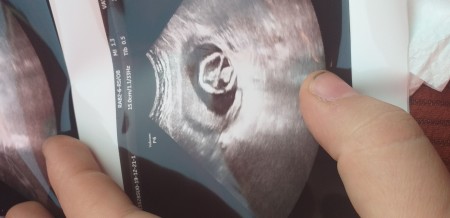

Kizlar bugun doktora gittm 16 haftalık gebeyim ve folik asit eksikligim den dolayi bebegimin basi ezik gibi duruyormus ve omurgasinda aciklik var dedi doktorum ve eli ayagi oynuyordu ķafasida oynuyordu  beni pazartesi riskli gebelikler uzmanina gondericekmis belki bebegi alabilmeyi soyler dedi boyle olup duzelen varmi  fotografini alta birakiyrm

Gebelik haftası 16